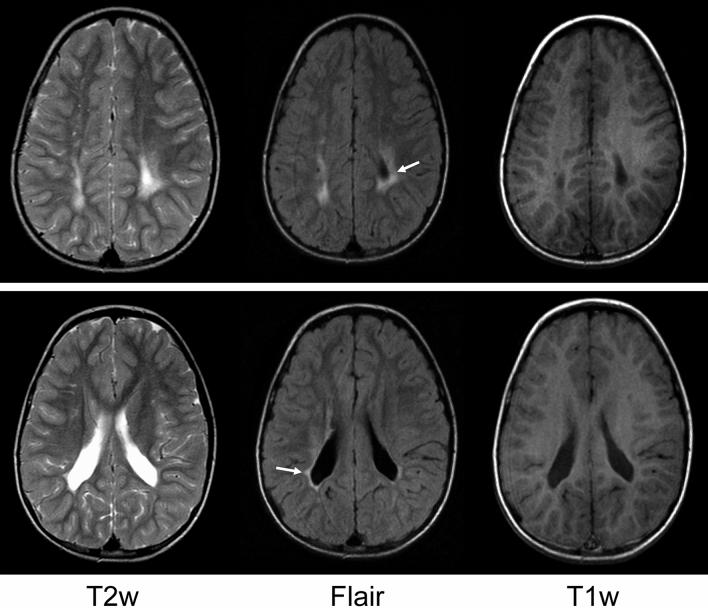

Faces hold a substantial value for effective social interactions and sharing. Covering faces with masks, due to COVID-19 regulations, may lead to difficulties in using social signals, in particular, in individuals with neurodevelopmental conditions. Daily-life social participation of individuals who were born preterm is of immense importance for their quality of life. Here we examined face tuning in individuals (aged 12.79 ± 1.89 years) who were born preterm and exhibited signs of periventricular leukomalacia (PVL), a dominant form of brain injury in preterm birth survivors. For assessing the face sensitivity in this population, we implemented a recently developed experimental tool, a set of Face-n-Food images bordering on the style of Giuseppe Arcimboldo. The key benefit of these images is that single components do not trigger face processing. Although a coarse face schema is thought to be hardwired in the brain, former preterms exhibit substantial shortages in the face tuning not only compared with typically developing controls but also with individuals with autistic spectrum disorders. The lack of correlations between the face sensitivity and other cognitive abilities indicates that these deficits are domain-specific. This underscores impact of preterm birth sequelae for social functioning at large. Comparison of the findings with data in individuals with other neurodevelopmental and neuropsychiatric conditions provides novel insights into the origins of deficient face processing.

面部在有效的社交互动和信息共享中具有重要价值。由于 COVID-19 相关规定,人们需要佩戴口罩遮挡面部,这可能导致他们难以使用社交信号,尤其是对于患有神经发育障碍的个体。对于那些早产儿来说,日常生活中的社交参与对他们的生活质量至关重要。在这里,我们研究了那些有早产儿出生史且存在脑室周围白质软化(PVL)迹象的个体(年龄为 12.79±1.89 岁)的面部敏感性。为了评估该人群的面部敏感性,我们使用了一种新开发的实验工具,即一组面部和食物的图像,这些图像的风格接近朱塞佩·阿尔钦博托 (Giuseppe Arcimboldo) 的作品。这些图像的一个关键优势是,单个组件不会引发面部处理。虽然大脑中似乎存在一个粗糙的面部图式,但前早产儿不仅在面部调节方面明显不足,与典型发育对照组相比,与自闭症谱系障碍患者相比也是如此。面部敏感性与其他认知能力之间缺乏相关性表明,这些缺陷是特定于领域的。这凸显了早产儿出生后遗症对社交功能的广泛影响。将这些发现与其他神经发育和神经精神疾病患者的数据进行比较,为理解面部处理缺陷的起源提供了新的视角。